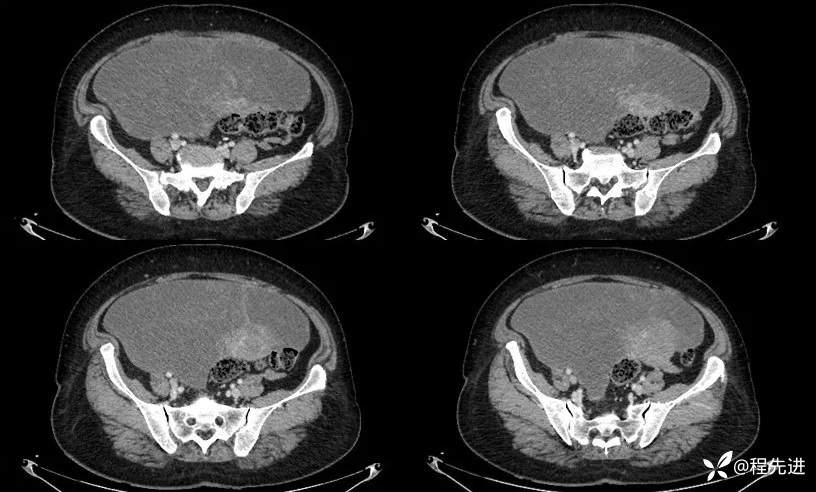

平扫:

门脉期: